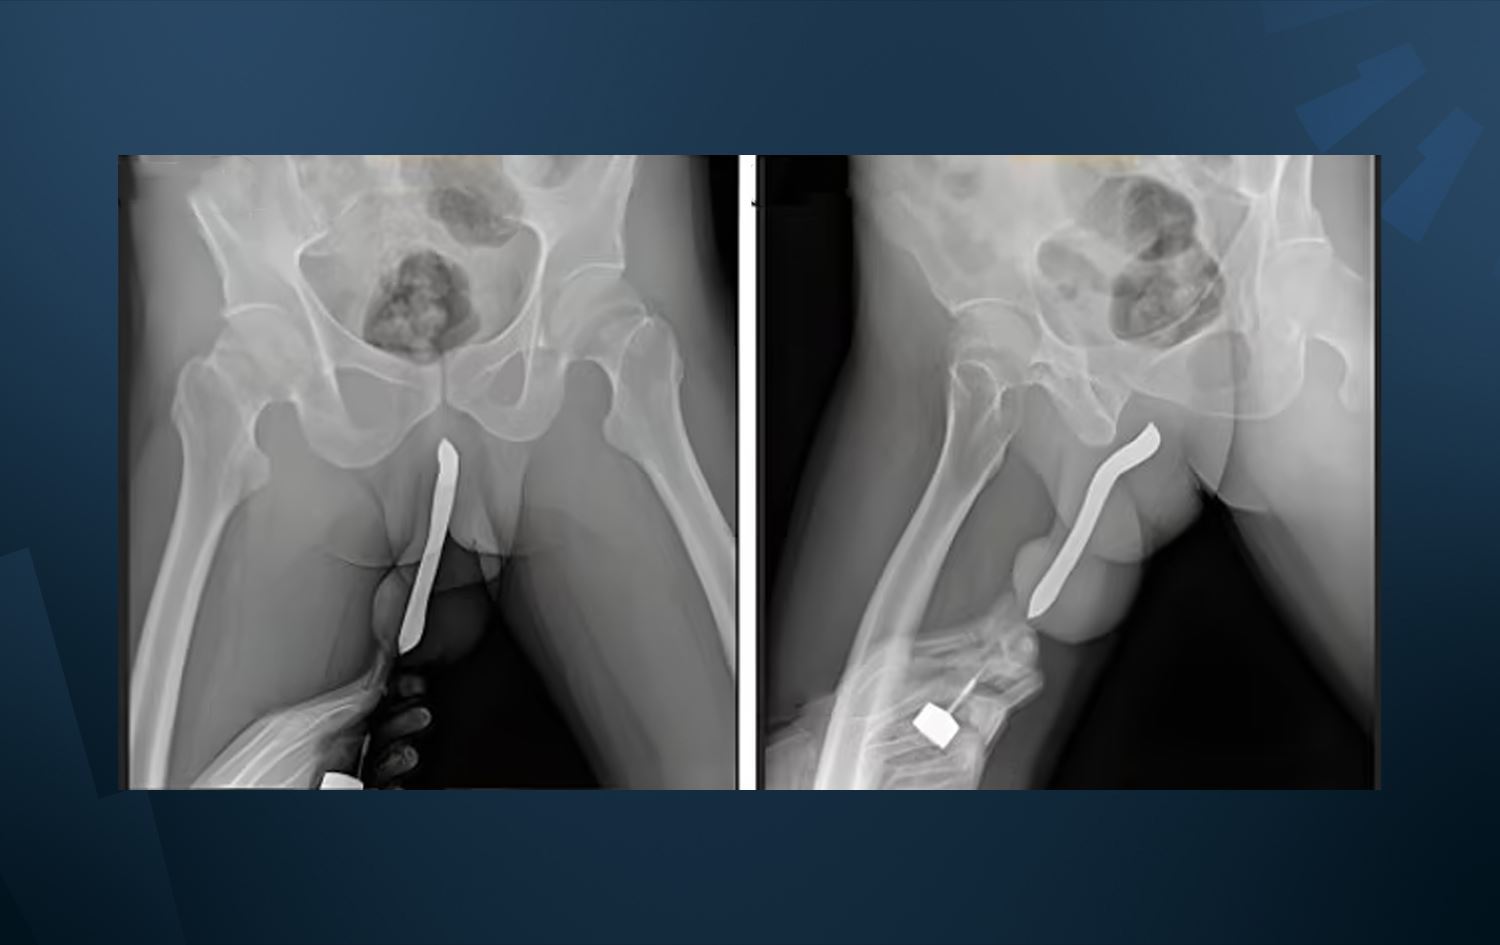

Endonezya'da 43 yaşındaki bir adam, “cinsel tatmini” artırmak için penisine diş fırçası soktu. Ancak önce fırça sonra penisi kırıldı.

Daily Mail'in haberine göre, Doğu Java'daki Soetomo Genel Akademik Hastanesi'ne giden şahıs ameliyata alındı.

Söz konusu şahıs 2017 yılında fırçanın yerleştirilmesini kolaylaştırmak için penisine küçük bir kesi bile yaptırdığını belirtti.

Doktorlara göre fırça, muhtemelen Endonezyalının partneriyle mutfak masasında seks yaparken kırıldı.

Ameliyata alınan şahıs iki saatlik başarılı bir operasyon geçirdi ve üç gün de hastanede yattı.